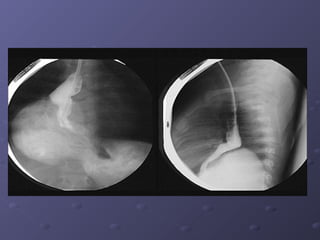

- X quangX quang : gợi ý tổn thương mờ, nang khu: gợi ý tổn thương mờ, nang khu

trú phía sau thùy dưới/ bn tái phát nhiềutrú phía sau thùy dưới/ bn tái phát nhiều

đợt.đợt.

Chẩn đoán hìnhảnhChẩn đoán hình ảnh - X quangX quang : gợi ý tổn thương mờ, nang khu: gợi ý tổn thương mờ, nang khu trú phía sau thùy dưới/ bn tái phát nhiềutrú phía sau thùy dưới/ bn tái phát nhiều đợt.đợt.